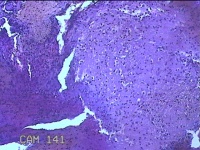

右侧卵巢囊肿

性别

女

年龄

临床诊断

一般病史

下腹痛3天。

标本名称

大体所见

灰白暗红色囊壁样组织2.5x1.5x0.3cm一块,表面糜烂,因已切开,囊内容物已流失,囊壁厚0.1cm。

图2